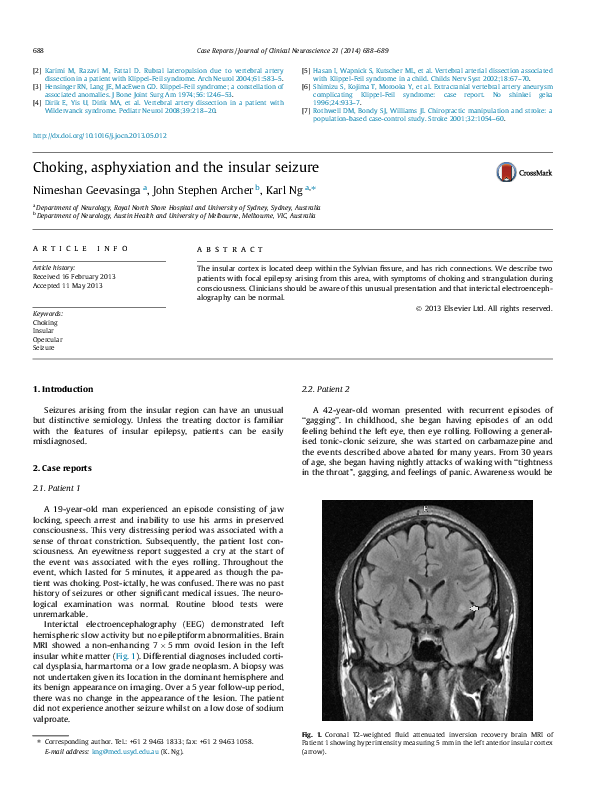

Asphyxiation essay picture This picture representes asphyxiation essay.